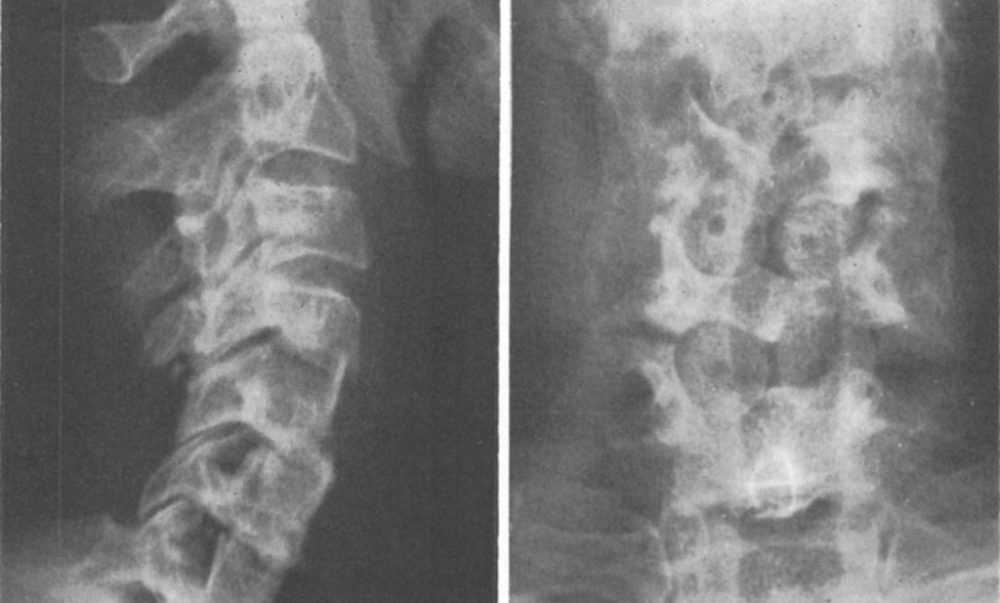

4) Spinal fusion